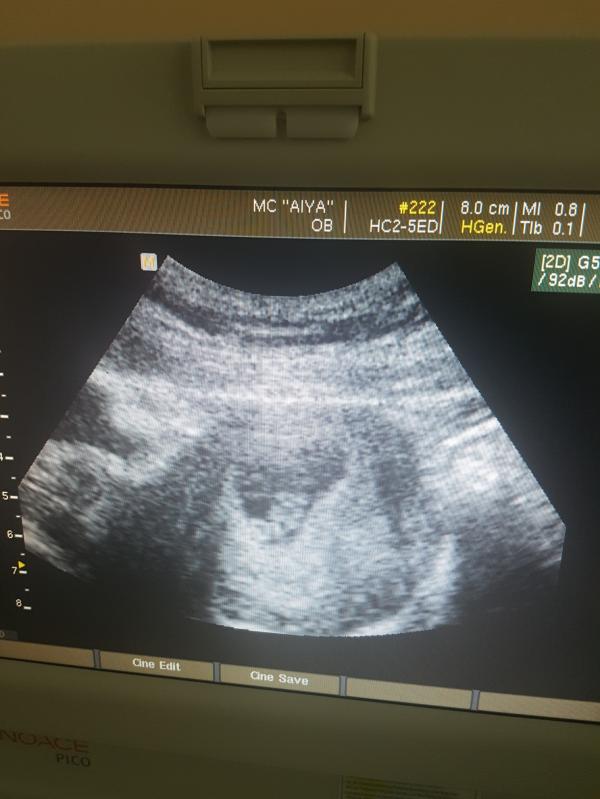

Девочки, страшно пздц! У меня неделю чесался живот, сдала анализы, сделали узи печени, а она сильно увеличина и не выдерживает нагрузки, еще и правая почка сильно страдает(( в общем врач приняла решения завтра меня кесарить. Меня всю трясёт, страшно до ужаса(( анастезия будет спиная. Успокойте меня пока я с ума не сошла((((все координально переигралось, хотела родить сама-фиг! С мужем были против парных родов, но завтра он будет со мной, первый увидет нашего малыша) завтра я стану мамой, завтра ...